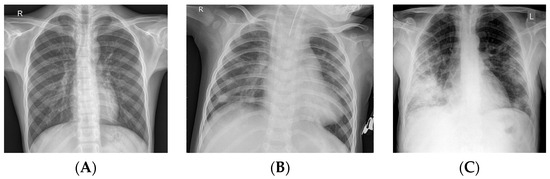

3.1. Dataset